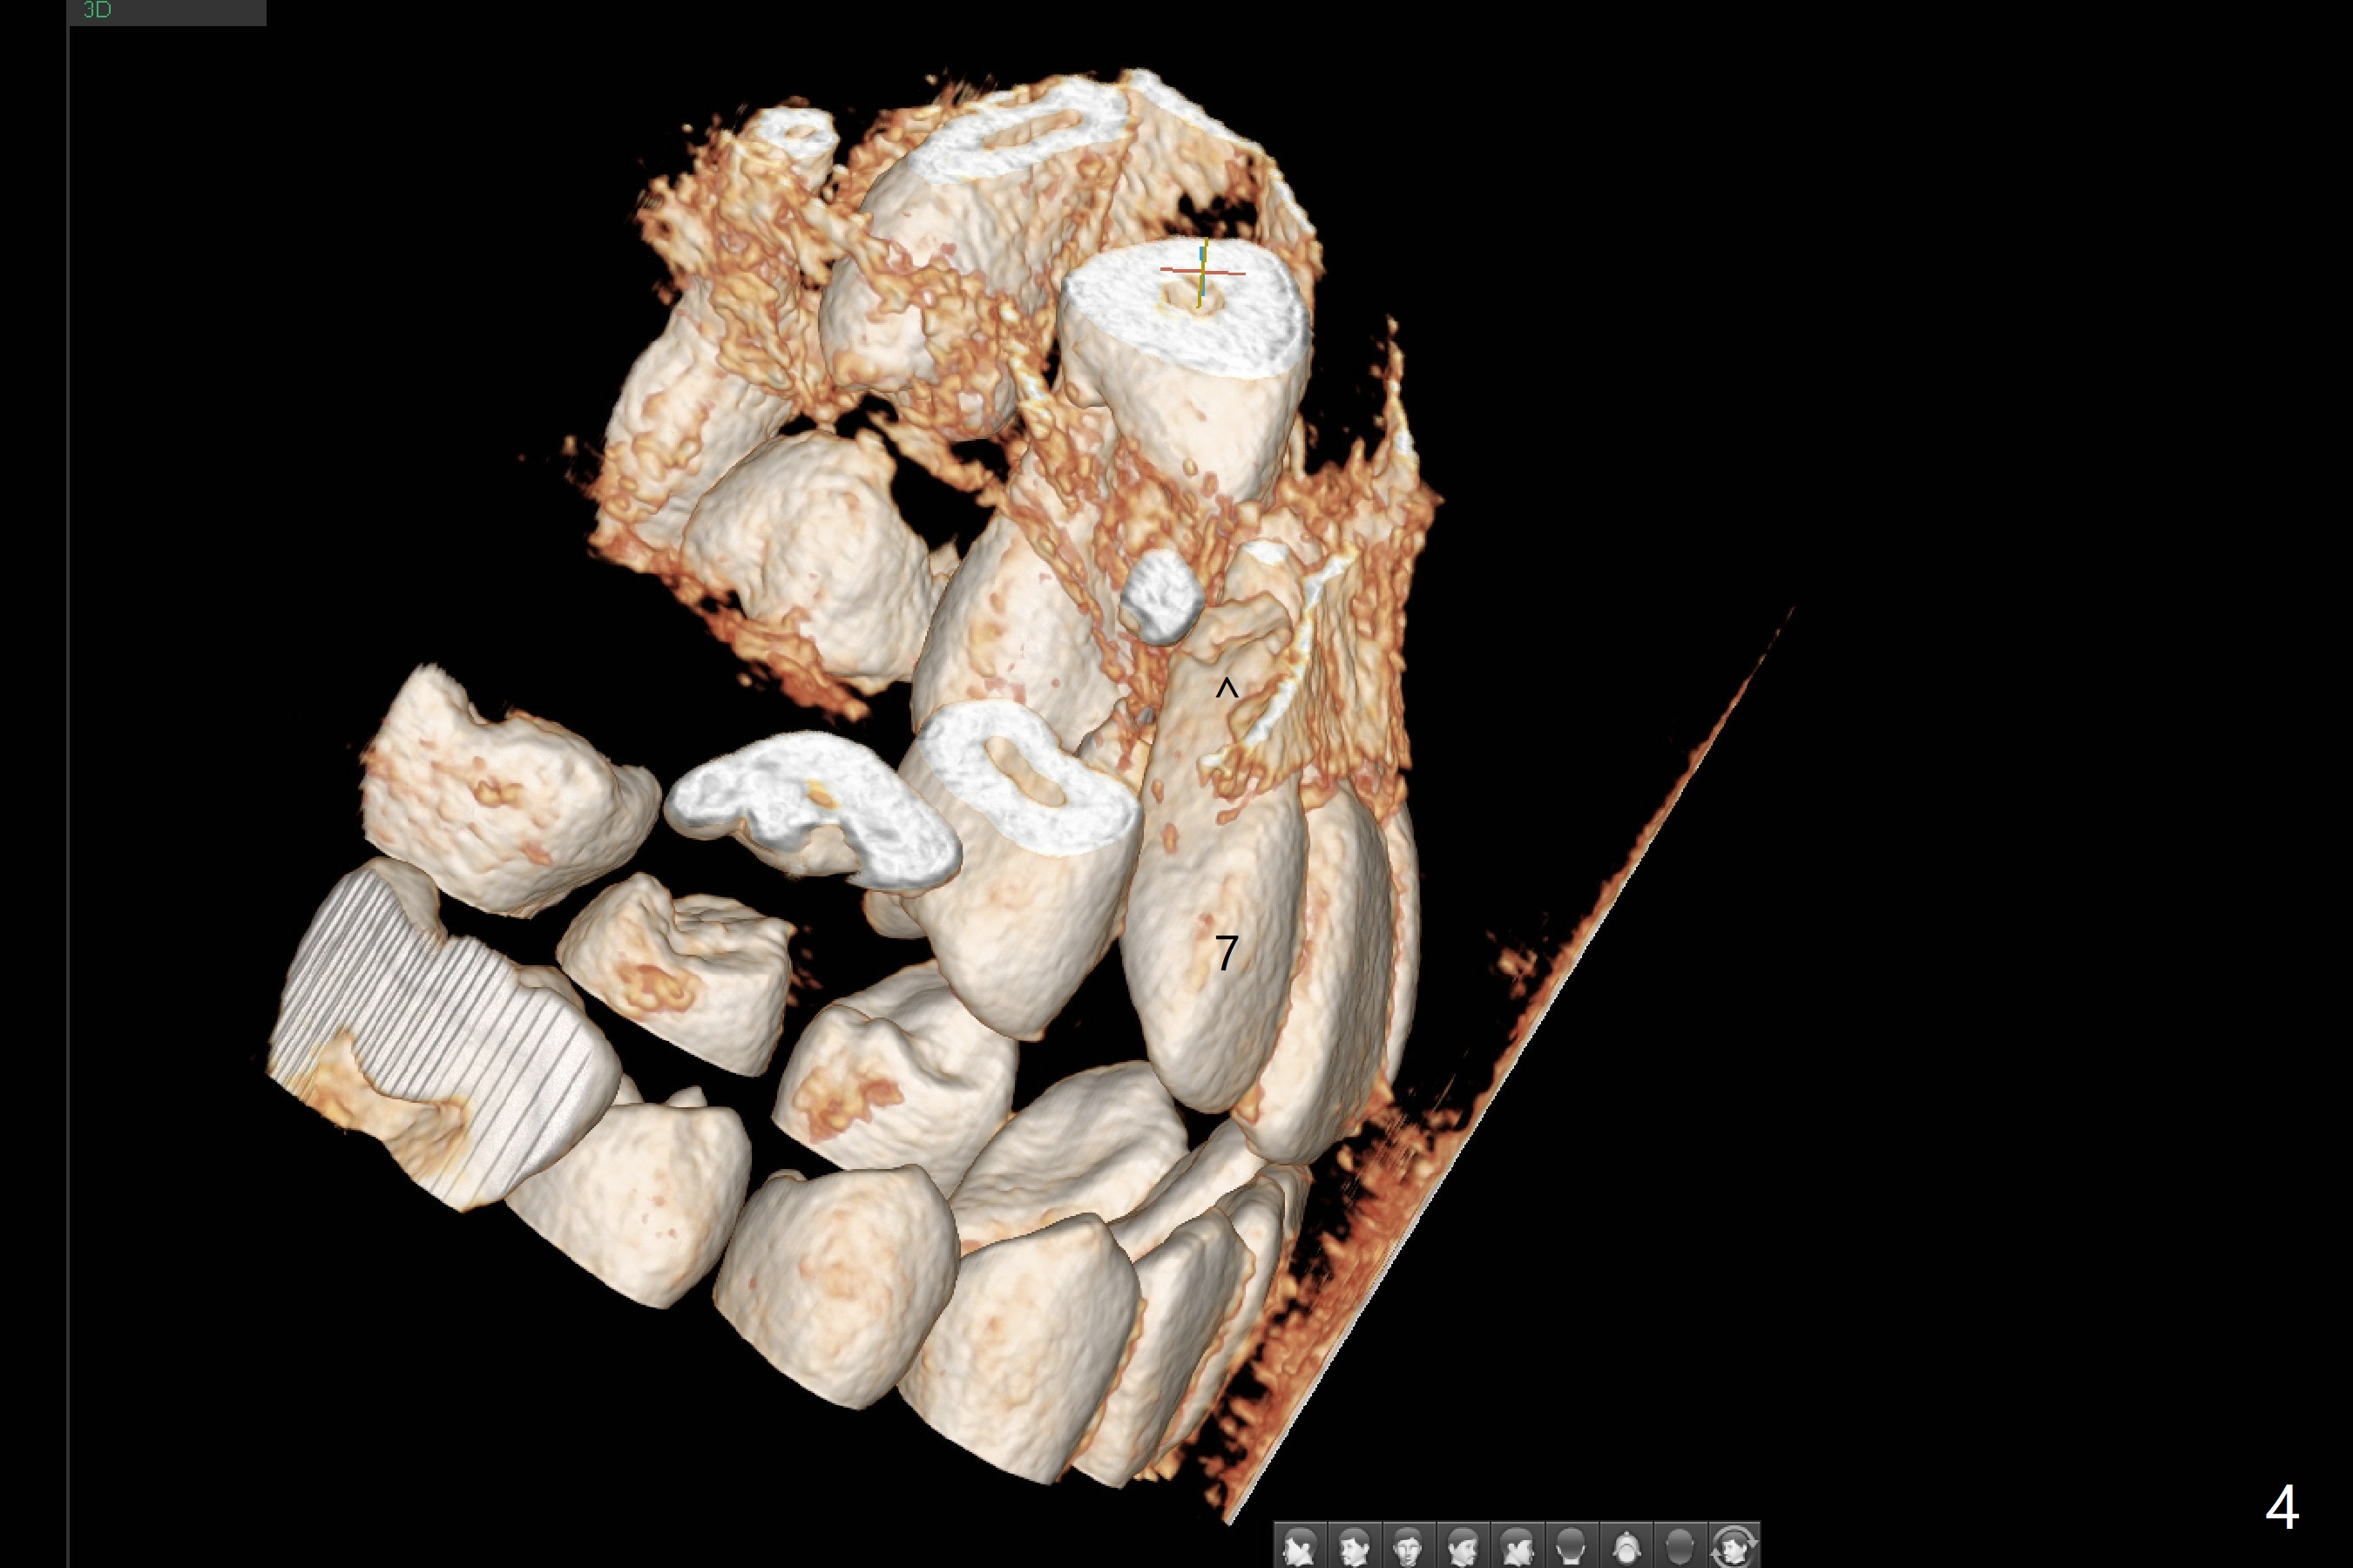

A 13-year-old boy with Class III malocclusion returns with mother from an orthodontic office for extraction of the tooth H with panoramic X-ray taken last year (Fig.1). An interesting finding was present, but not diagnosed a year earlier (Fig.2).

A cystic lesion around each of the impacted permanent upper canines. A normal dental sac or dentigerous cyst?